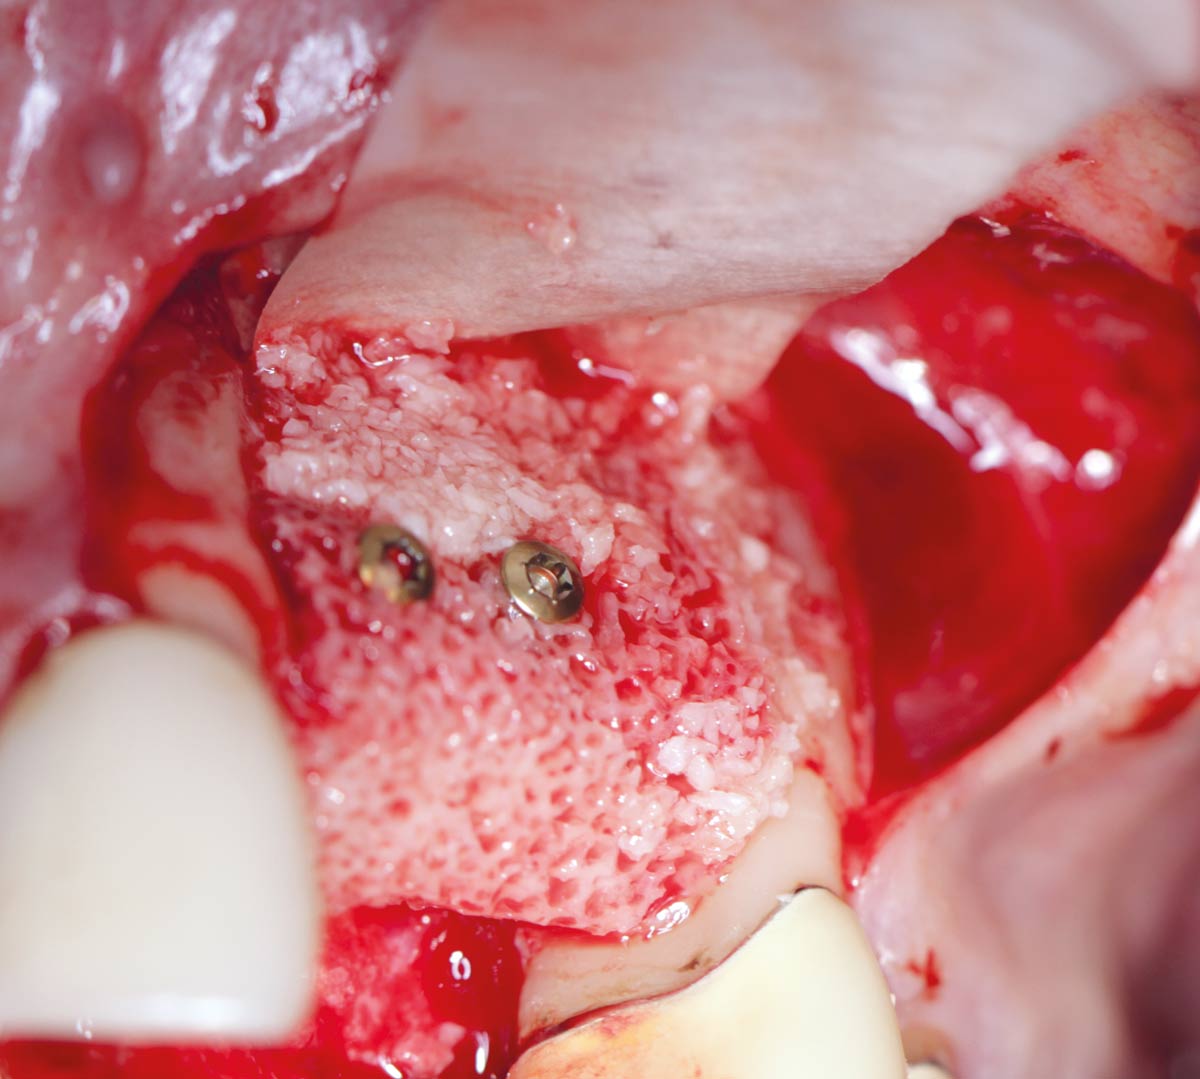

Simultaneous GBR and implantation using maxgraft® granules and autologous bone